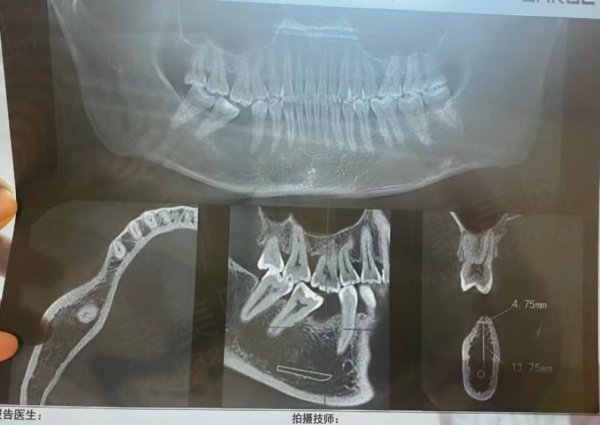

西安团圆口腔为了不断提高自己的口腔诊疗技术,引进了大量国外先进设备如:德国产CBCT数字牙科机、意大利进口全景X光机、美国产牙科CAD/CAM系统等,能够为西安广大群众带来全新的数字化诊疗体验,享受业界较为前沿的口腔诊疗技术。

网友种植牙评价1

网友种植牙评价2